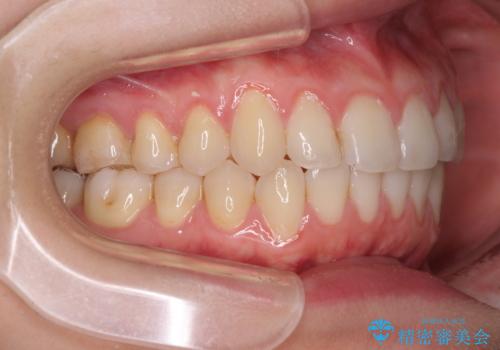

- 上下前歯のデコボコを気にして来院された患者様です。

インビザラインによる上下歯列の側方拡大と後方移動、IPR(歯と歯の間を削る)にるスペースの獲得により歯列を整えることとしました。

1日22時間の装着時間をしっかり守ってくださったので、予定していた1年よりも早く治療を終えることができました。

インビザライン矯正特有の奥歯がしっかりと咬合しない感覚も改善され、大変満足していただきました。